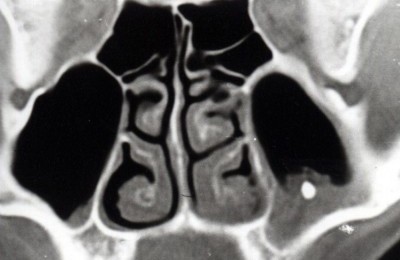

МРТ

После осмотра больному предоставляется возможность сделать рентген гайморовых пазух или МРТ.

Поскольку, часто симптомы наличия инородного тела в пазухе отсутствуют, пациенты приходят сделать МРТ головного мозга и случайно обнаруживается постороннее тело в носовой пазухе, что является полной неожиданностью.